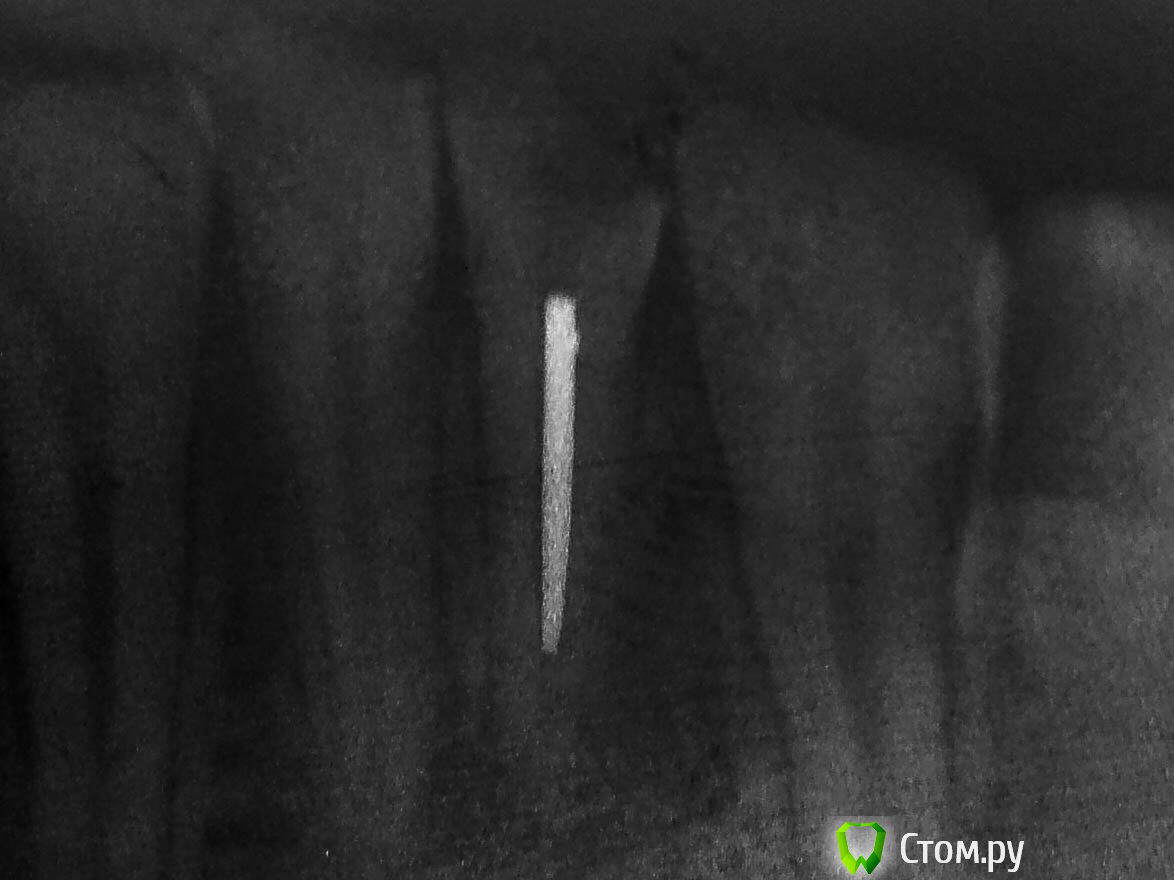

Alexandr Iv Опубликовано 29 июля, 2014 Поделиться Опубликовано 29 июля, 2014 Пациент Н. 14 лет.Диагноз: Хронический гранулирующий периодонтит зуба 3.1Зуб ранее дважды лечен эндодонтически. Корневой канал "обтурирован" проволокой. Был направлен на удаление. Хирург пригласил на консультацию. Решили "спасать". За час под микроскопом извлечена проволока (наверно, это проволока)) ) методом захвата в самодельный цилиндр (из носика для жидкотекучего) и заклиниваем проволоки в цилиндре с помощью 25 к-файла. Обработка и обтурация корневого канала. SoftCore + несколько дополнительных штифтов. Восстановление коронки зуба Filtek Ultimate. Каков на Ваш взгляд прогноз зуба и как Вы видите дальнейшее восстановление коронковой части? Ссылка на комментарий

Alexandr Iv Опубликовано 21 ноября, 2014 Автор Поделиться Опубликовано 21 ноября, 2014 Контрольный осмотр через 4 месяца.Жалоб нет. 2 Ссылка на комментарий